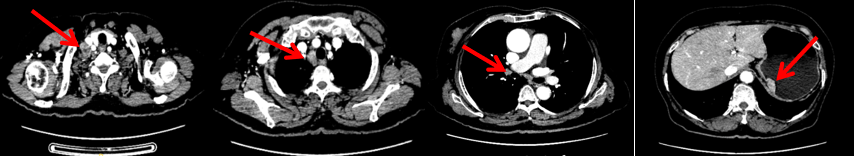

2023.6.26复查PET-CT

1.右乳外上象限乳腺癌病灶(22*16mm),对比2023-04-14 CT(26*24mm)较前缩小,FDG代谢活跃。右侧腋窝小淋巴结(5mm),较前稍缩小,代谢不活跃。右侧锁骨上区、上纵隔淋巴结转移瘤(24*18mm),现大小同前相仿,代谢活跃(SUV:6.7)。

2.现胃贲门部术后改变,术区未见明显异常活性灶。

3.左乳、左侧胶窝术后改变,未见明显异常活性灶。双肺小结节。考虑炎性结节可能,建议复查;双肺门及纵隔另反应性淋巴结。

患者已接受胃癌根治术,术后通过PET-CT对病灶情况进行了评估。目前患者采用哌柏西利联合氟维司群方案治疗,乳腺病灶已明显缩小,但锁骨上淋巴结、纵隔及肺门淋巴结未见缩小。为进一步为患者制定更精准的治疗方案,龚畅教授与曾银朵教授组织了第二次多学科联合会诊。